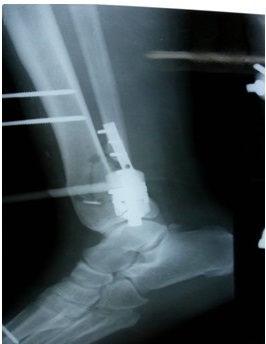

Como parte del plan quirúrgico trazado se realizó la limpieza quirúrgica requerida y se optó por la colocación de un fijador externo monopolar en puente para controlar la fractura del pilón, al montaje referido se le asoció una placa semitubular de un tercio de caña de seis perforaciones para estabilizar la lesión peroneal. (Figuras 4, 5, 6, 7).

Tras la cirugía, el paciente permaneció internado en Servicio de Ortopedia y Traumatología, con tratamiento antibiótico de amplio espectro y se empleó la terapia antitrombótica protocolizada en la institución. Pasados siete días de la cirugía se egresó el paciente y a partir de ese momento comenzó su seguimiento en la consulta externa de nuestro centro.

La consolidación de la fractura se obtuvo a las 12 semanas, el fijador externo se mantuvo todo este tiempo y afortunadamente los resultados finales fueron considerados satisfactorios tras la culminación del periodo de fisioterapia. (Figura 8).